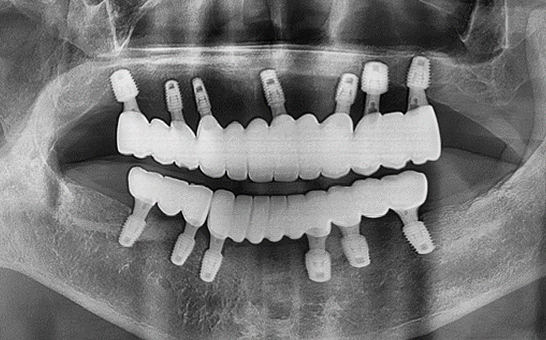

CASE 01 김** / 60대

전악임플란트

치료 시작 전 촬영 2024.01.24 | 치료 완료 후 촬영 2024.12.26

1 예후불량 치아 발치

2 발치 후 즉시 임플란트 식립 및 뼈이식

3 고정성 보철물로 수복 후 일상 회복